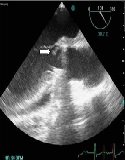

Ralstonia pickettii-Infected Endocarditis Complicated with Possible Septic Emboli in Kidney: A Rare Case Report